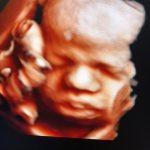

3D

Je baby in stilstaande beelden met perspectief en kleur. Een 3D echo is een stilstaand beeld van een levensechte weergave van jouw kindje. Hierbij zijn duidelijke contouren zichtbaar van bijvoorbeeld de vingertjes, het neusje en de lipjes.